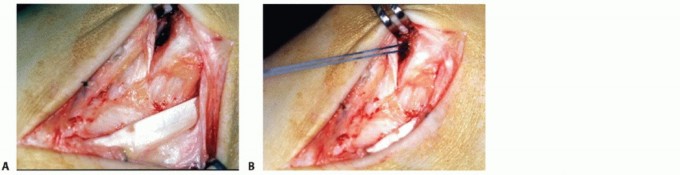

TECH FIG 8 • Chronic rupture of the deep deltoid ligament. A. Exposure of the posterior tibial tendon reveals a tear. B. Exposure of the deltoid ligament reveals an extended disruption and incompetence of the superficial and deep layers. C. A bone-tendon-bone transplant is fixed by screws distally into the navicular bone and, after tightening, proximally to the posterior aspect of the medial malleolus. D. Multiple nonabsorbable and absorbable sutures are used for further reconstruction of the ligament.

However, this technique was found to be disappointing, as it does not sufficiently reinforce the deep tibiotalar ligaments (Hintermann, unpublished data, 2012). Most recently, the use of a bone-tendon-bone

transplant has been proposed for reconstruction of the deltoid ligament (TECH FIG 8).2 In this in vitro study, two limbs were created on a distal transplant; one was fixed to the medial aspect of the talus and the other to the sustentaculum tali. The proximal end was fixed to the distal tibia, the medial malleolus, or the lateral tibia. Less than 2.0 degrees of angulation was found while applying valgus stress of 5 daN for all fixation methods. However, the authors advised against fixation of the proximal limb to the medial malleolus.